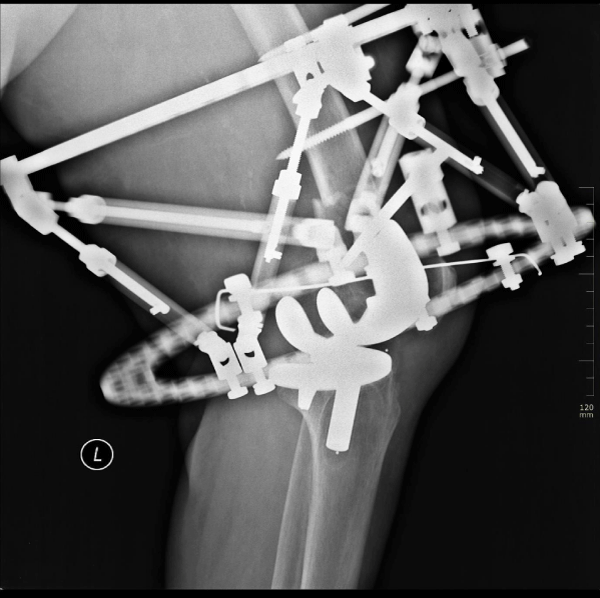

With the patient under Laryngeal Mask Airway (LMA) anesthesia, a CACEF System (The Smart Correction ®) was applied (Figure 3). The fixator was performed with the patient in the supine position under image-intensification guidance. Two half-pins and a tensioned wire were inserted through the distal ring and distal to the fracture line. Two half-pins were inserted into the proximal ring and proximal to the fracture line. The device consisted of 6-strut construct for connection of special frames. We didn’t make any effort for reduction intra operatively. So operative time was just 35minutes. The patient tolerated surgery well and made rapid recovery postoperatively.

Figure 3: Radiograph showing the management of the fracture by computer assisted circular external fixation.

We made computer assisted frame adjustments postoperatively very quickly and she began passive and active range-of-motion (ROM) exercises and partial weight bearing with crutches on the postoperative next day. She was instructed to increase weight bearing and ROM exercises as tolerated. She was discharged from hospital after the maintenance of stability and followed up in routine manner with monthly intervals. The fixator was removed 12 weeks later after sufficient callus formation was noted on radiographs and partial weight bearing protocol was used for protection for an additional two weeks (Figures. 4 and 5). After one year, she had 0-120º of motion and was satisfied with the clinical result and had minor complaints such as weakness, numbness related to other co-morbidities.